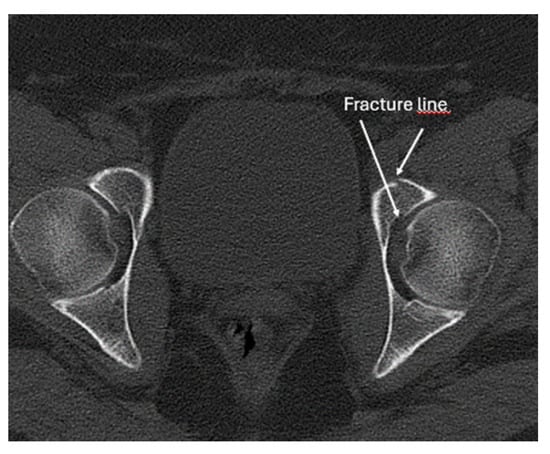

- Screening for fractures and hematoma during the primary survey in Advanced Trauma Life Support (ATLS), particularly in polytrauma patients, ultrasound enables rapid identification of fractures that are associated with life-threatening hemorrhage (e.g., pelvic or femoral fractures).

- Screening of fractures in the primary ATLS (Advanced Trauma Life Support) survey that are associated with or may cause life-threatening bleeding in polytrauma

- Recommendation 4: The E-FAST protocol, indicated for severely injured patients in shock, should be expanded to include fracture screening of long tubular bones and open-book fractures when the torso scan is negative for free fluid. This could identify hidden injuries and bleeding.

- In E-FAST, which is indicated for moderately to severely injured patients with shock, it can be expanded to fracture screening of long tubular bones and open-book fractures if the result of the torso scan is negative for free fluid.